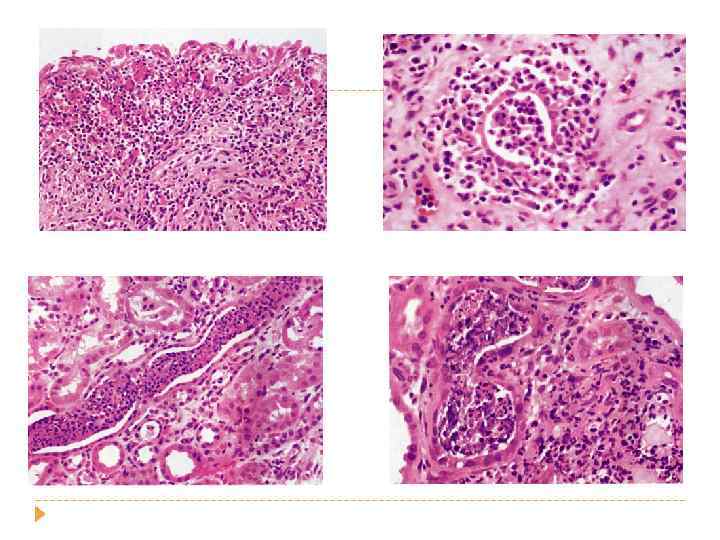

острый пиелоне фрит Гнойное воспаление с абцедированием Хронический пиелонефрит Лимфогистиоцитарная инфильтрация и склероз стромы, Перигломерулярный склероз Кистозная атрофия канальцев «тиреодизация почки» Ассиметричное сморщивание почек с грубыми рубцами